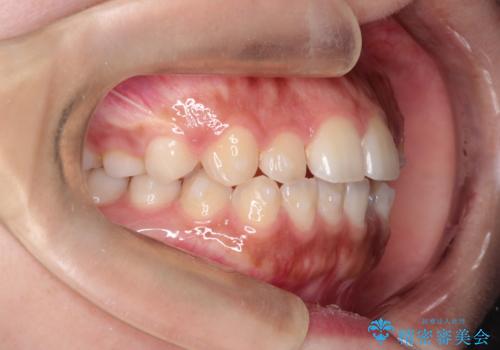

インビザライン 前歯のがたつきを目立たず矯正

- 前歯のがたつきが気になるとのことで来院されました。

インビザラインにて治療を行いました。

わずかに歯と歯の間に隙間を作り、歯列矯正を行いました。

マウスピースをしっかりと使用していただけたので、スムーズに治療を終了することができました。